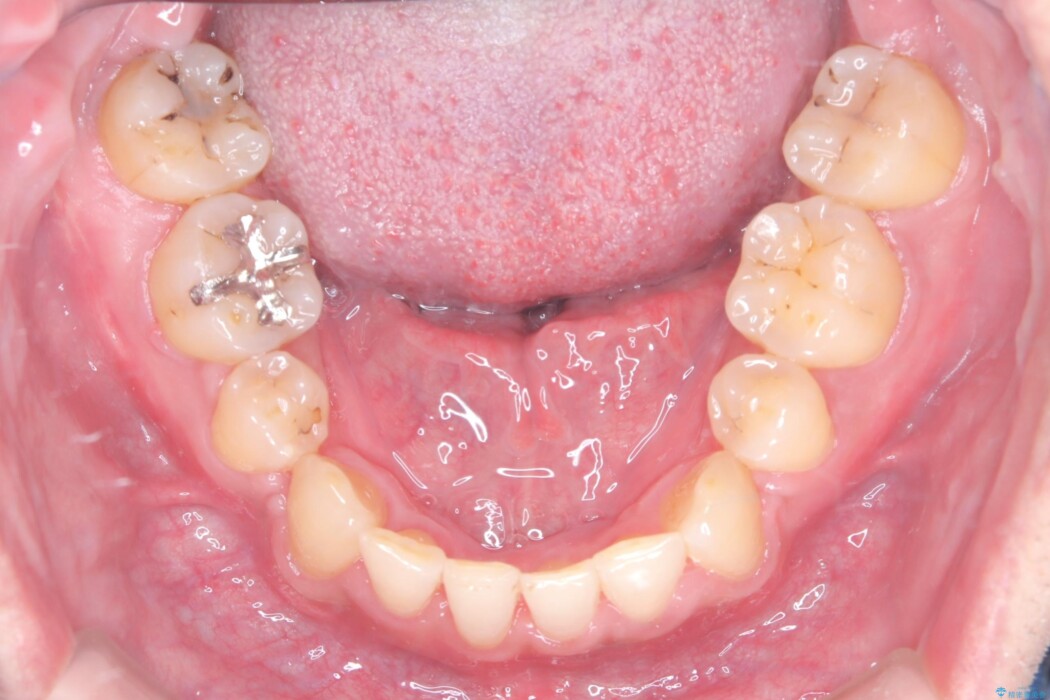

反対になっている嚙み合わせを改善したいとご来院されました。

診査の結果、上下左右4番の歯を抜歯し、審美装置にて反対咬合と叢生を改善していくこととしました。

骨格性Ⅲ級を示しましたが、構成咬合位がとれたことから反対咬合と叢生改善のため、上下左右第一小臼歯を抜歯しワイヤー矯正を行いました。途中、バイトアップを行っています。